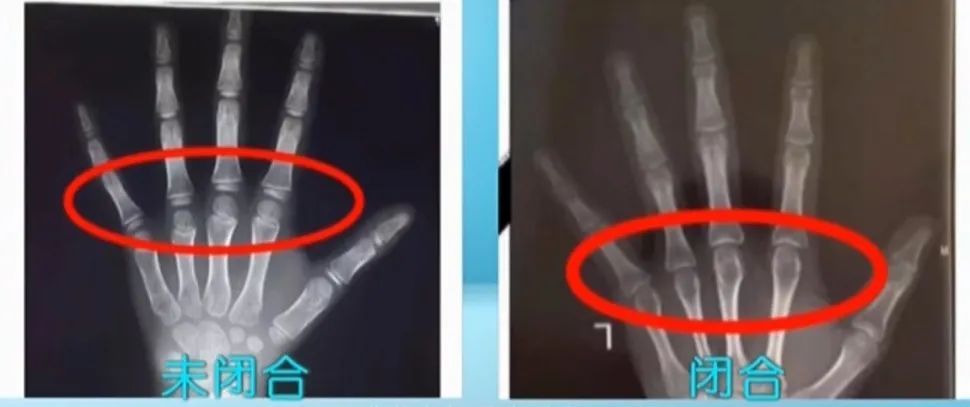

过去由于营养不太好,青春期推迟,所以有“23岁还能窜一窜”的说法,但现在普遍的营养好,女孩一般14岁骨龄就接近闭合了,男孩16岁闭合。想要知道孩子的骨龄,可以前往医院拍左手正位片。

早诊断,早治疗,效果更好。并且骨龄闭合后,生长激素就不能用了。